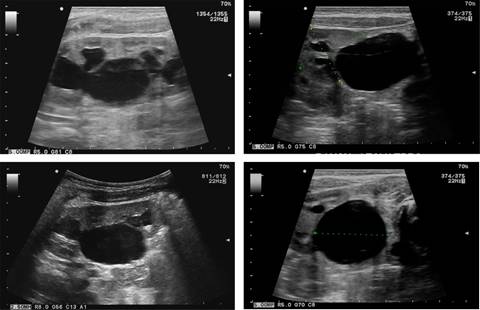

Recién nacido (un día) masculino, urología pediátrica solicita ultrasonido renal debido a que en el ultrasonido prenatal se observa hidronefrosis izquierda, único hallazgo descrito. El ultrasonido renal postnatal muestra hidronefrosis grado III unilateral que termina abruptamente en la unión ureteropiélica, el resto del trayecto del uréter no se observa dilatado, ya que presenta un calibre normal; el parénquima renal está intacto, sólo adelgazado (Figura 1).

Figura 1: Ultrasonido renal en escala de grises que muestra hidronefrosis grado III, existe dilatación de la pelvis (2.7 cm) y de los cálices renales, con una transición abrupta del calibre ureteral en la unión ureteropiélica; el resto del diámetro ureteral se mantiene aparentemente normal. El parénquima renal está adelgazado, pero permanece intacto, las dimensiones renales están moderadamente agrandadas.